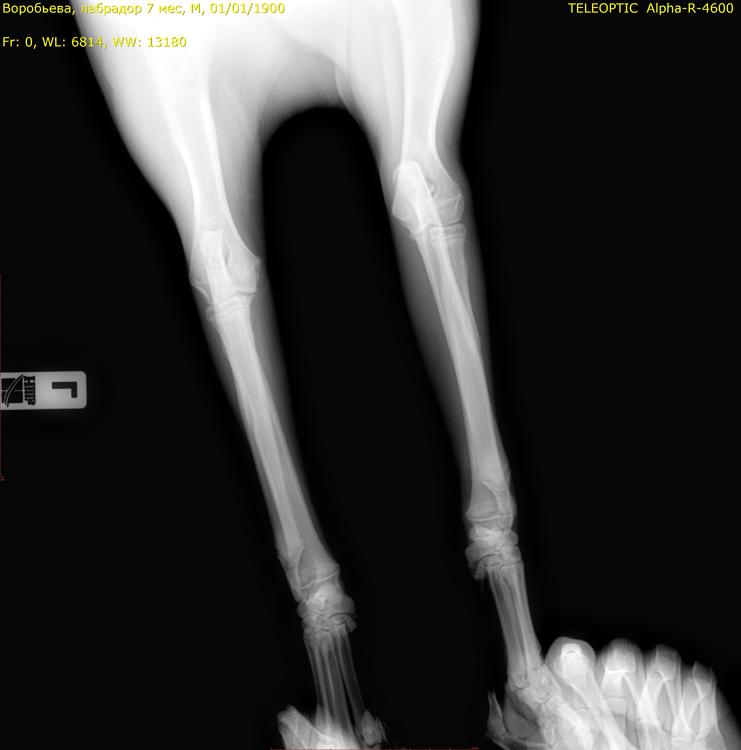

сделали рентген, ничего не нашли. но собака хромает. день сильно хромает день слабо. потом вообще не хромает, может долго не хромать. прошло полторы недели она побегала сильно и снова начала лапа сильно хромать передняя. дали таблетки превикокс, сказали если через неделю опять будет хромать, то возможно дисплазия и надо будет делать артроскопию или компьютерную томографию. я не знаю что это может быть. снимки ниже - но не все уместились9999_00015491.jpg.445e6e663116dbc373a10d9bc5e488da.jpg9999_00015492.jpg.1483c792e930011ebb0e20b405812211.jpg

Начальная стадия может быть не видна на рентгене, при этом есть периодическая хромота. Не давайте скакать и беситься строго. Нельзя играть с собаками. Шаг и спокойная рысь на поводке до постановки точного диагноза.